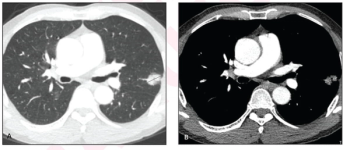

An AI model that includes extracted radiomic features from CT scans more than doubled the sensitivity rate for preoperative prediction of lung cancer recurrence in comparison to traditional TNM staging, according to study findings to be presented at the 2024 American Society of Clinical Oncology (ASCO) Annual Meeting in Chicago.

In comparison to pure solid nodules in patients with non-small cell lung cancer (NSCLC), nodules with a minor ground glass opacity component were associated with over a 38 percent higher rate of recurrence-free survival.

One deep learning model had a 72.4 percent accuracy rate for differentiating between benign and malignant solid pulmonary nodules on non-contrast CT while another deep learning model demonstrated an 87.1 percent AUC for differentiating benign and inflammatory findings.